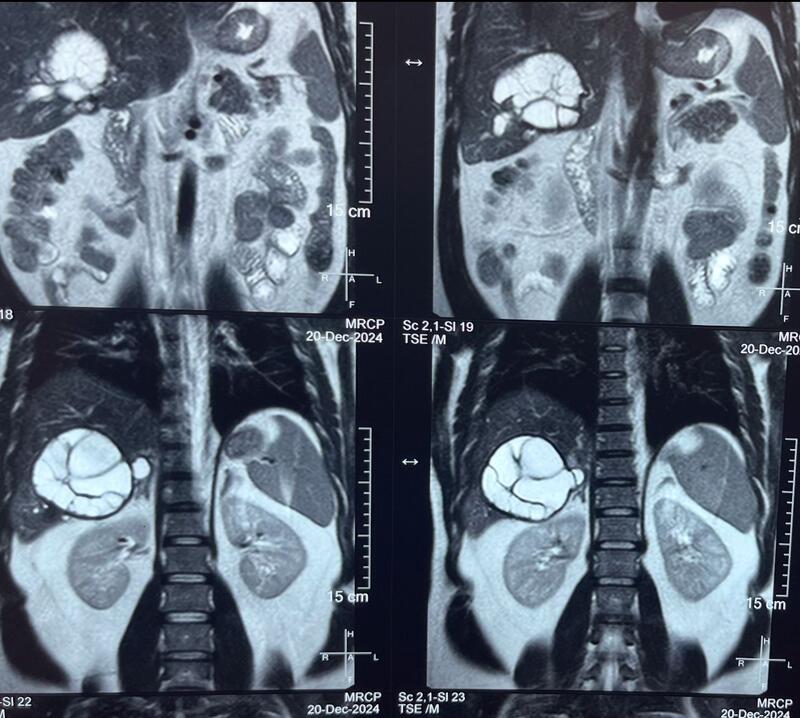

Blood investigations showed obstructive jaundice. CT Abdomen and pelvis with MRCP confirmed a large hydatid cyst in the right lobe of the liver measuring 12x14 cm, compressing the right biliary ducts (posterior ducts), with no obvious biliary communication. Associated cholecystitis with sludge in the gallbladder was also noted.